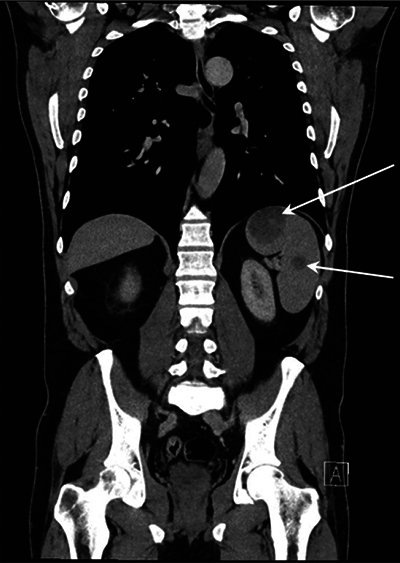

Epithelioid hemangioendothelioma (EHE) is a rare vascular tumor that can originate in various parenchymatous organs, soft tissue, and bone. Extrahepatic involvement is exceedingly rare. In this case, multifocal disease in the spleen and bone was present. Bone lesions showed a target appearance. Splenic lesions showed delayed enhancement of solid components with persistent rim enhancement. A bone biopsy with CAMTA1 staining confirmed the diagnosis. Teaching point: The presence of multifocal bone and splenic lesions can raise suspicion of EHE when other multifocal diseases are excluded.

上皮样血管内皮瘤(EHE)是一种罕见的血管肿瘤,可起源于各种实质性器官、软组织和骨骼。肝外受累极为罕见。在该病例中,脾脏和骨骼出现多灶性病变。骨病变呈靶状。脾脏病变显示实性成分延迟强化,边缘持续强化。经CAMTA1染色的骨活检确诊。教学要点在排除其他多灶性疾病的情况下,出现多灶性骨和脾病变可引起对 EHE 的怀疑。